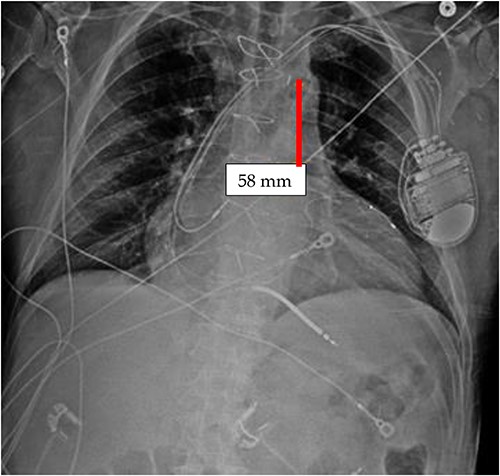

TEE guidance and fluoroscopy were used during the insertion of this patient’s left axillary IABP. The TEE note post-IABP insertion states that ‘the balloon is seen from the distal end of the aortic arch extending into the descending aorta.’ A same-day post-insertion CXR in the ICU showed a shortened IABP at about 5.1 cm long, indicating that the balloon must have been folded over itself to allow both markers to be so close to each other (Fig. 4).

Initial CXR: note the proximal and distal radiopaque markers of the IABP are visualized a few centimeters (5.1 cm) from each other; the proximity of the two markers indicates that along the path of the IABP, it has folded over itself causing the two markers to be abnormally close, as the 8Fr. balloon is 258 mm long, thus the markers should be separated by that much.

It appears that the IABP became mispositioned after its initial placement as seen on follow-up CXR (Fig. 4). Despite almost daily CXRs, this IABP mispositioning was missed by the managing team and radiologists, probably due to interference from the automatic implantable cardioverter defibrillator (AICD) leads, EKG leads, and sternal wires. Twenty-one days later (Fig. 5), the radiologist erroneously read that the IABP had been removed, so CXRs were never repeated. Figure 5 shows that the IABP was still folded over itself but now with a shadow in the arch/ascending aorta from the migrated IABP.

CXR done 21 days later, which shows the markers still not properly placed but the distance is about the same (5.8 centimeters) as the original position; additionally, the shadow of the inflated helium balloon can be seen in the ascending and aortic arch.